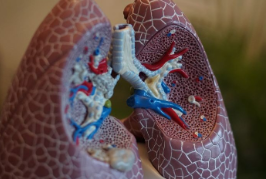

폐암 이란?

폐암은 말 그대로 폐에 생긴 악성종양을 의미합니다. 크게 소세포폐암과 비소세포폐암으로 나뉘는데, 대부분의 폐암환자분들은 비소세포폐암에 해당됩니다. 전체 폐암 중 80~85%가량 차지하며, 편평 상피세포암, 선암, 대세포암등이 속합니다.